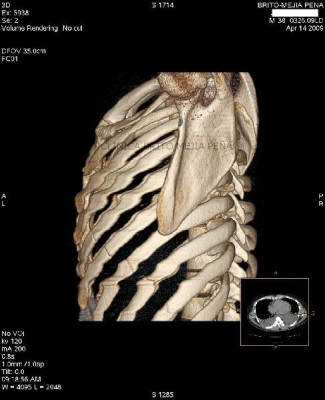

Fracturas costales

Post Image

Fracturas en esternón y costillas